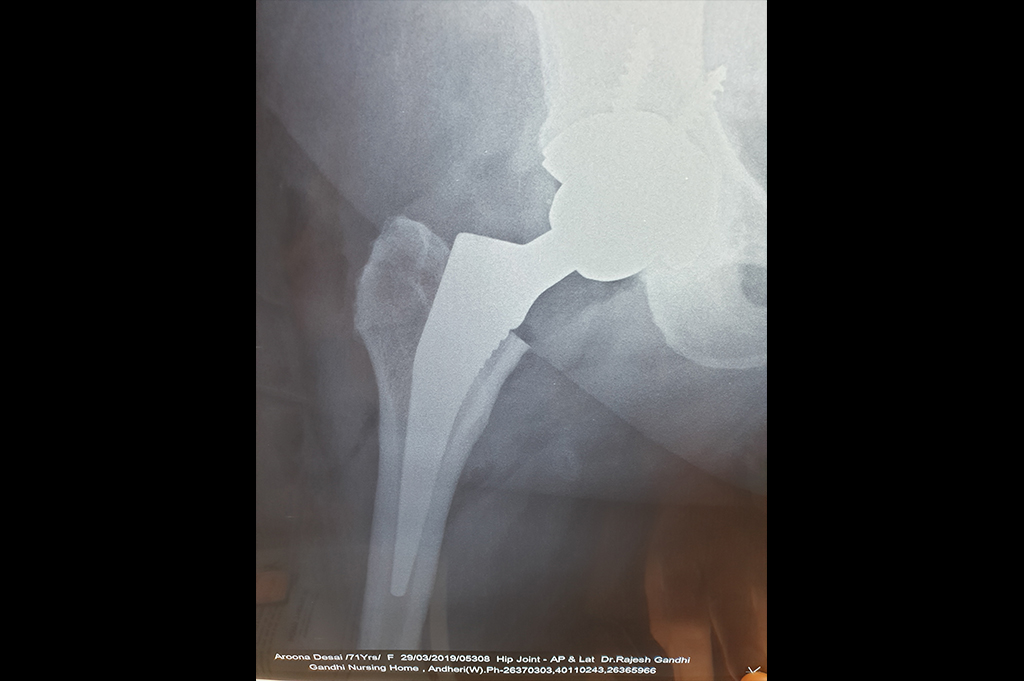

Total Hip Replacement - THR